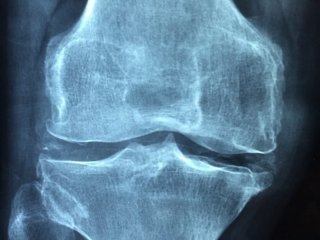

콘드로이친은 연골의 탄력을 유지해 관절 마모를 예방하며, 무릎이나 허리 통증 등의 관절염 증상을 완화하는 데 효과적입니다.

콘드로이친은 염증 유발 물질의 생성을 억제해 만성 염증을 줄이고 관절 주변의 붓기를 완화합니다. 특히 퇴행성 관절염 환자에게 유익합니다.

콘드로이친은 연골세포의 활성을 돕고 콜라겐 합성을 촉진해 손상된 연골 조직을 재생하는 데 도움을 줍니다.